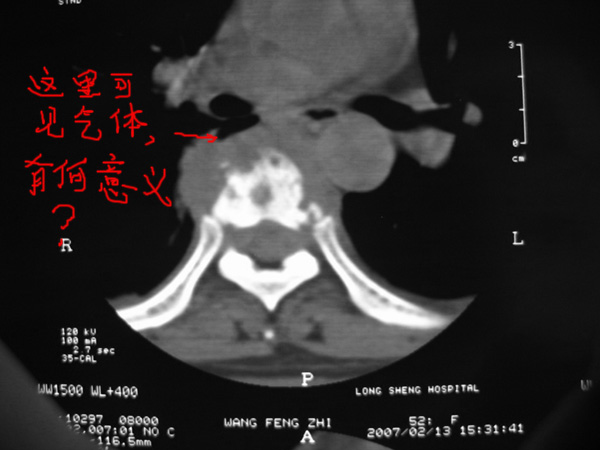

椎旁肿胀的软组织内可见气泡影,对脊柱的化脓性和结核性的鉴别有帮助吗?

楼主所指应该是奇静脉食管窝中的肺组织

胸椎结核与脊柱椎体化脓性脊柱炎,从影像特点很难鉴别,本例具有二者的共性特点,建议结合临床鉴别以下,我考虑:1 化脓性脊柱炎.2 胸椎结核.原因:1 椎旁脓肿内含气泡.2 椎体溶骨性破坏,但未见死骨.

胸椎结核与脊柱椎体化脓性脊柱炎,从影像特点很难鉴别,本例具有二者的共性特点,建议结合临床鉴别以下,我考虑:1 胸椎结核.2 化脓性脊柱炎.原因: 椎体溶骨性破坏,但未见死骨.我认为大家说的气泡是假象。